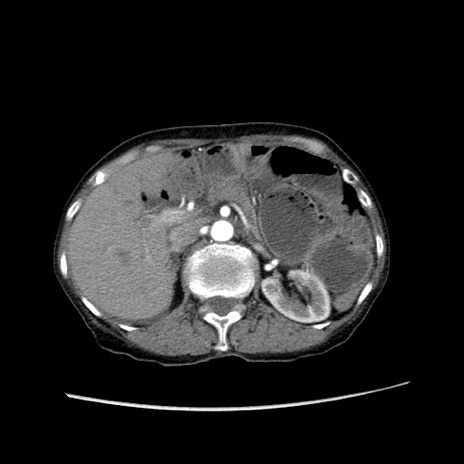

症例25(横断像)

【症例】80歳代女性

【主訴】胸のつかえ感

【現病歴】約9時間前に食後から胸のつかえた感じあり、嘔吐あり、来院。

【既往歴】胃癌(全摘)、胆摘、虫垂炎

【身体所見】心窩部に圧痛あり、反跳痛なし。

【データ】WBC 5700、CRP 0.05